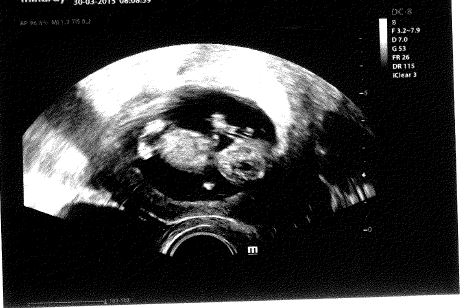

Já mám z posledně tento obrázek (je tam hlavička, tělíčko, obě ručky a nožky). Miminko bylo otočené přímo čelně proti ultrazvuku

. Tak se mě to líbilo. Je to pomocí vnitřního ultrazvuku.

Ještě mám jednu, tam je mimčo jako mimozemšťan. Tu mi doktor udělal jako první, tak jsem říkala, že tu nechci, že chci tu ručičkama a nožkama

Doktorovi se víc líbila tahle.... Dostala jsem nakonec obě.

Ale na téhle je vidět hlavně hlavička (částečně průhledná) a jsou tam vidět oči po stranách.